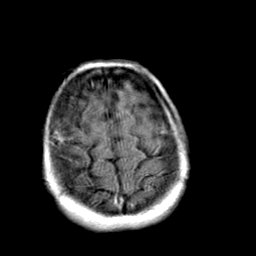

Creutzfeld-Jakob disease: gadolinium enchanced T1-Weighted MR -- Slice #20

[Home][Help][Clinical] Slice 20